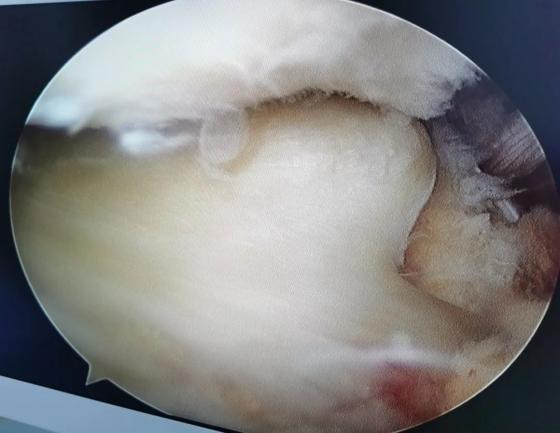

退行性半月板病变部分切除术